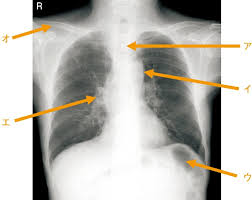

人体の構造と機能及び疾病の成り立ち : 看護師国家試験 管理栄養士国家試験 徹底解説

診療放射線技師国家試験 対策ノート